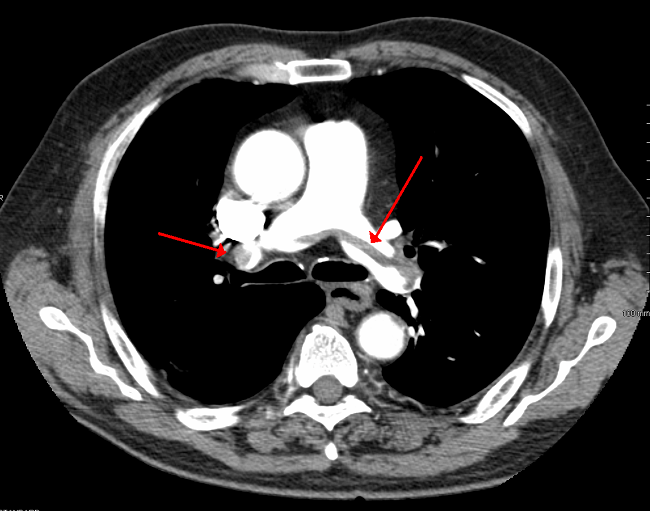

Doctors found out after examination Kimberly was suffering from bilateral pulmonary embolisms and that her lungs were filled with blood clots. Doctors praised Camdyn’s insistence on Kimberly coming to them, as if she had decided to nap it off, she may never have woken up again. Doctors kept Kimberly in hospital care for seven days and gave her meds to resolve the clotting issue. However, it would take upto six months for the clots to go away and two years for Kimberly to be fully healthy again.

Image Source: www.wikimedia.org